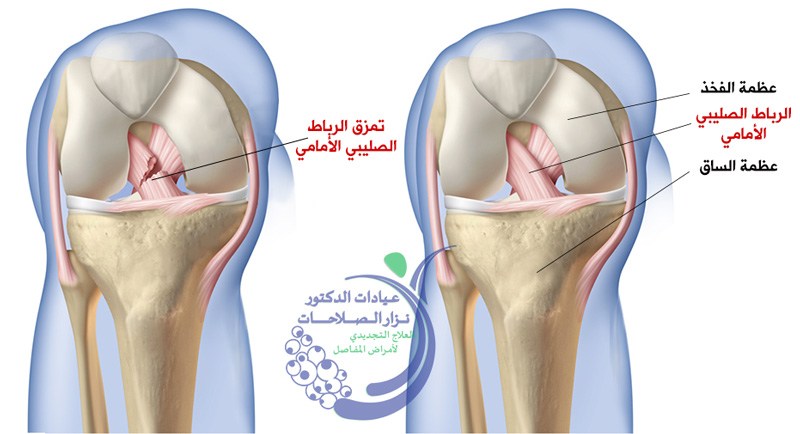

علاج قطع الرباط الصليبي الجراحي والغير جراحي

علاج قطع الرباط الصليبي والذي بدوره ينتج من تعرض الفرد للاشخاص المُمارسين للرياضة بشكل مُستمر مثل لاعبي كرة السلة وكرة القدم. في الحالات التي يتعرض فيها الرباط الصلي